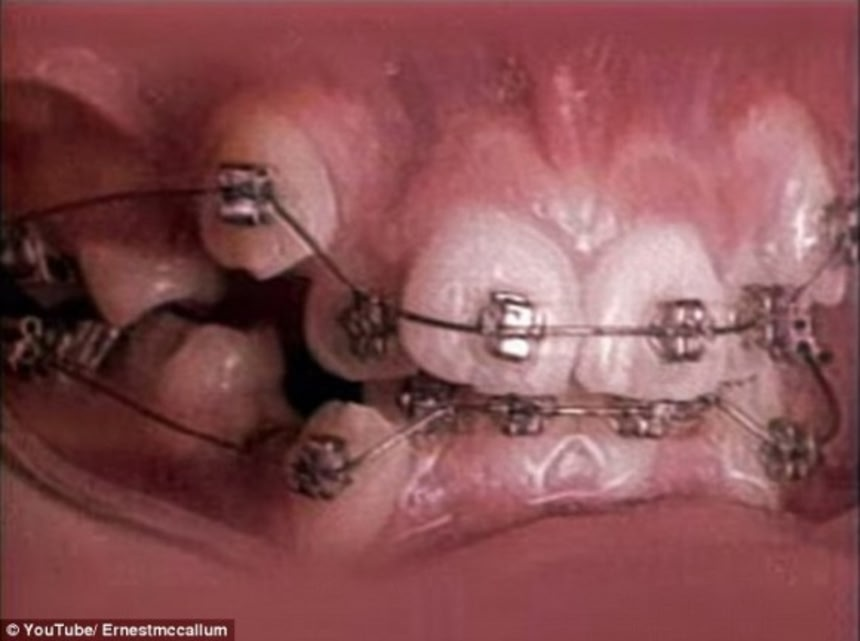

この動画では11歳の少女が18ヶ月間受けた矯正治療を25秒に短縮した早回しで見ることができる。矯正ワイヤーで不揃いだった歯がどんどん移動して整列する様子がよくわかる。

治療前:ガタガタしていた歯並びに矯正用のワイヤーが取り付けられている。

この画像を大きなサイズで見る歯科矯正は歯に圧力をかけて移動させる治療法だ。昔ながらの矯正器具はブラケット、接着剤、アーチワイヤー、そしてOリングと呼ばれるブラケットとワイヤーを固定する輪ゴムの4つの部品からなる。

歯の表面に接着したブラケットの上にアーチワイヤーで締めて歯を移動させる。歯を決まった方向に引っ張るOリングが使われる時がある。

装着後、アーチワイヤーの圧力は1ヶ月置きのペースで調整されるのが普通だそうだ。理由は時間をかけて正しい力をゆっくりとかけるため。歯に圧力をかけると歯根膜が片側に張り出し、もう一方が圧縮されるという。

移動した歯を支えてくれる新しい骨が育つように歯を緩める。その過程は骨を強化する生体力学的な工程で、歯根のリモデリングと呼ばれる。

また、締めつける力が強すぎるのもダメだ。歯が緩むのが早すぎて、新しい骨の成長が追いつかなくなり、歯を失ってしまうことがあるからだ。